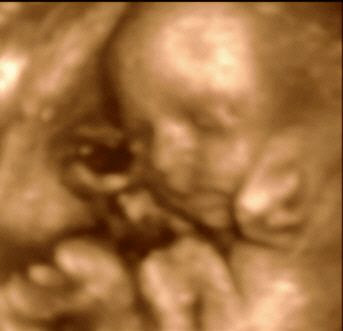

Here is a close up of Z’s face…I think she has my nose…

Here she is, curled up and kicking it…